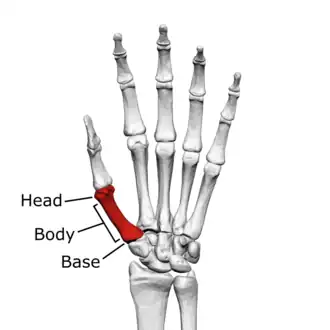

Head

The head is less rounded and less spherical than those of the other metacarpals, making it better suited for a hinge-like articulation.

The distal articular surface is quadrilateral, wide, and flat; thicker and broader transversely and extends much further palmarly than dorsally. On the palmar aspect of the articular surface there is a pair of eminences or tubercles which articulate with the radial and ulnar sesamoid bones of the thumb metacarpophalangeal joint; the lateral eminence is larger than the medial.

Body/Shaft

The body or shaft is thick and broad — averaging 6 to 11 millimetres (0.24 to 0.43 in). On its dorsal side, the shaft is flat and wide, while the anteroposterior side is less pronounced; usually resulting in an oval-triangular cross-section.

The dorsal surface of the shaft is weakly convex longitudinally, while its palmar, radial, and ulnar surfaces tend to be concave. The palmar and medial surface exhibits a blunt ridge which separates a larger lateral part – the insertion of the opponens pollicis muscle – and a smaller medial part – the origin of the lateral head of the first dorsal interosseous muscle.

Base

The base is significantly different from the bases of the other metacarpals. It is trumpet-shaped and ends in a saddle-shaped articular surface matching that of the trapezial articular surface. The configuration of the thumb carpometacarpal joint plays an important role in the mechanism of opposition. The articular surface is delimited by a thick, crest-like ridge extending around its circumference.

On the palmar and lateral side of the base is the insertion of the tendon of the abductor pollicis longus muscle, usually featuring a small tubercle. The origin of the first dorsal interosseous muscle is on the ulnar aspect of the base, and can sometimes extend onto the shaft. In contrast to the other metacarpals, the first metacarpal has no articular facets on the sides of its base (for intermetacarpal articulations) because it articulates exclusively with the trapezium.